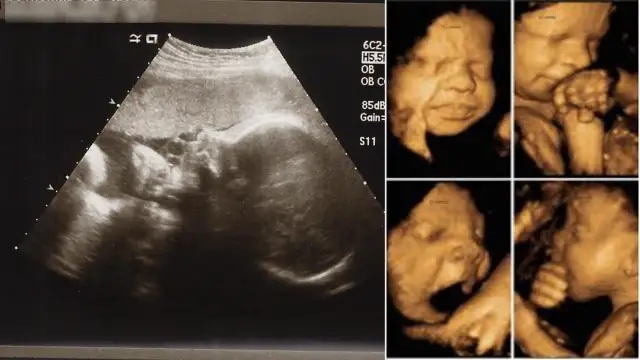

Kiedy badanie prenatalne: kluczowe terminy i co musisz wiedzieć

Dowiedz się, kiedy badanie prenatalne jest kluczowe w ciąży. Poznaj terminy i ważne informacje, które pomogą Ci zadbać o zdrowie matki i dziecka.